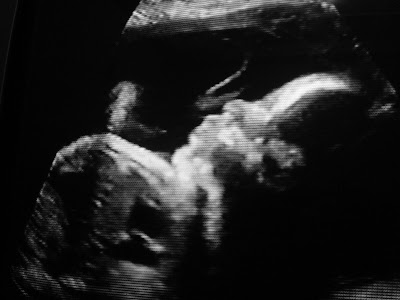

Semana passada tive pré-natal dos 8 meses. Tudo normal, com exceção da proteinúria que vai ser avaliada esta semana com novo exame de urina. Engordei menos de 4kg nos 8 meses de gestação (estranho isso, mas o médico não disse nada). Na primeira consulta pré-natal, com 2 meses de gestação, eu estava com 62.7kg e na última consulta, com 8 meses de gestação, 66.1kg, ou seja, engordei 3,4kg até hoje! Se continuar assim, não vou ganhar nem 5kg em toda a gravidez! Será que isso é normal? Acho que o médico não falou nada porque meus exames de sangue estão normais e a barriga tem crescido dentro da tabela. Clara também está com peso e tamanho normais para a idade gestacional (34 semanas): 2.525kg e 44 cm. Faltam ainda 6 semanas, acho que ela vai nascer com mais de 3kg se chegar até o final...

Olha o tamanho das bochechas dela:

Não me canso de olhar pra ela, rs.